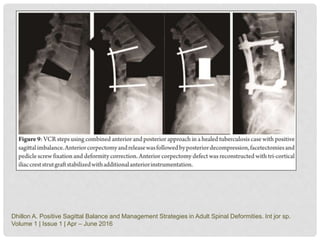

• Classification of progression (Rajasekaran):

A treatment algorithm to guide selection of appropriate posterior approach

osteotomies based on the classification presented in the study. PSO = pedicle

subtraction osteotomy, DBO = disc bone osteotomy, and VCR = vertebral column

resection.

S. Rajasekaran- J Bone Joint Surg Am. 2018;100:1147-56

• Treatment

 Operative procedures:

• anterior decompression/corpectomy, strut grafting ± posterior

instrumented stabilization ± posterior column shortening

Dhillon A. Positive Sagittal Balance and Management Strategies in Adult Spinal Deformities. Int jor sp.

Volume 1 | Issue 1 | Apr – June 2016